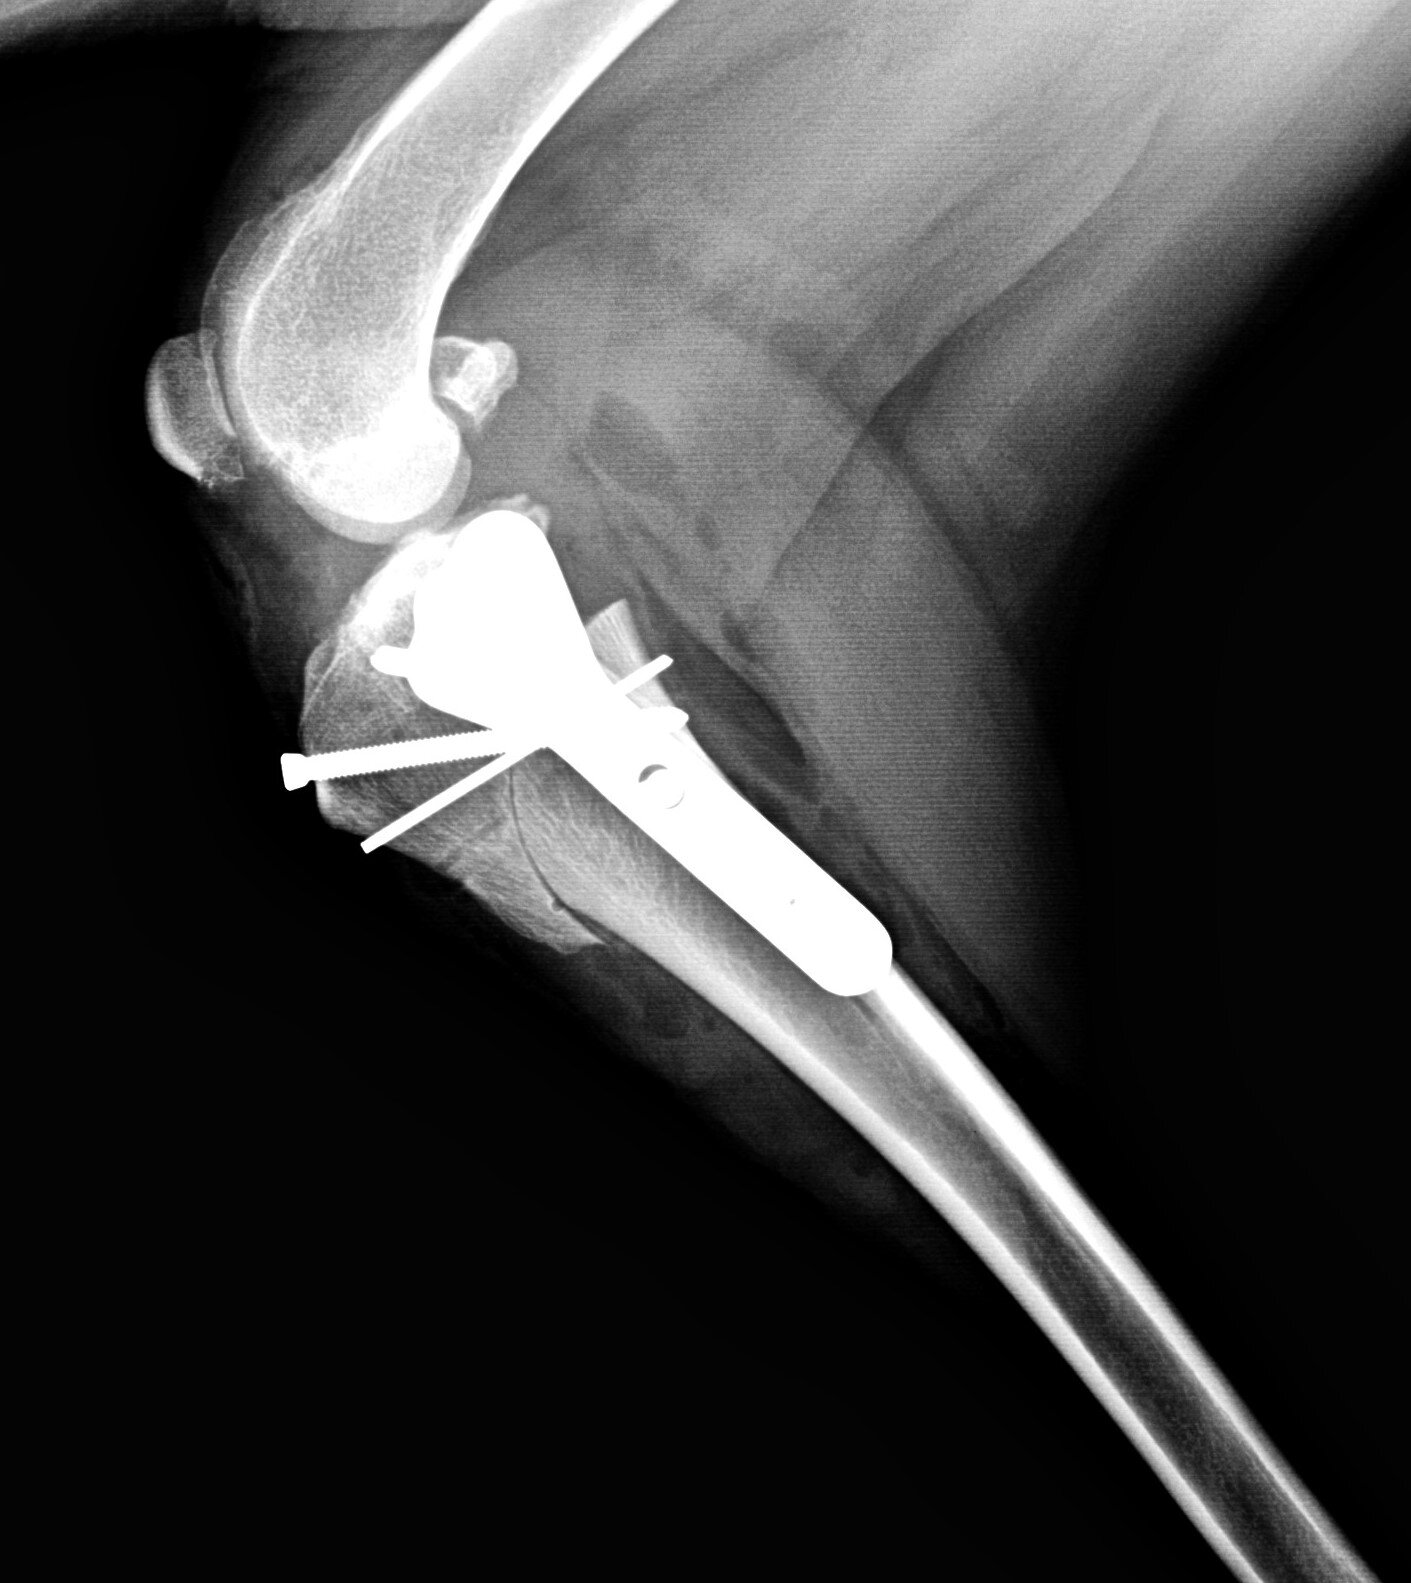

• Orthopedic Surgery: The hospital provides advanced orthopedic surgery for conditions such as hip dysplasia, cruciate ligament injuries, and fractures. The surgical team is experienced in performing complex procedures to restore mobility and function.

TPLO — Warm Springs Pet Hospital